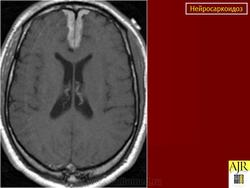

ID: 17921 Neurosarcoidosis Dr Frank Gaillard - 25 May 2012 The case demonstrates typical features of neurosarcoidosis, which are of...

Случай 1: с участием лептоменинга

Случай 2: с участием паренхимы

Случай 3

Случай 4: вокруг гипофизарного стебля

Случай 5: вовлечение спинного мозга

Случай 6: вовлечение гипофизарного стебля